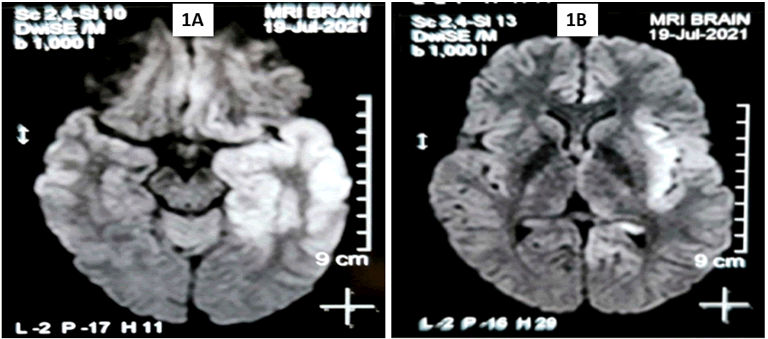

His complete blood count, blood sugar levels, renal and liver function tests, chest radiography and electrocardiography testing were within normal limits. His blood and urine culture, dengue and malaria serology were negative. Cerebrospinal fluid (CSF) analysis revealed protein-104.7 mg/dl, cell count-27(100% lymphocyte) and glucose 47 mg/dl. Magnetic resonance imaging (MRI) brain revealed T2W/FLAIR hyperintensities in left temporal lobe, left orbitofrontal lobe and left insular cortex with gyral swelling in right temporal lobe (Figure 1). Real time polymerase chain reaction (PCR) testing of CSF was positive for Herpes Simplex Virus 1. A final diagnosis of HSE was made. Intravenous acyclovir 500 mg three times a day was given for 21 days. Injection levetiracetam and lacosamide were continued. On day 18 of admission, his GCS improved to E4V5M6. No further episodes of fever and seizures occurred. On higher mental function testing at discharge (day 23), lexical fluency, calculation, registration and recall were impaired.

Figure 1. Magnetic resonance imaging of brain showed hyperintensities in left temporal lobe, left orbitofrontal lobe and left insular cortex (1A and 1B) with associated gyral swelling in right temporal lobe (1A).